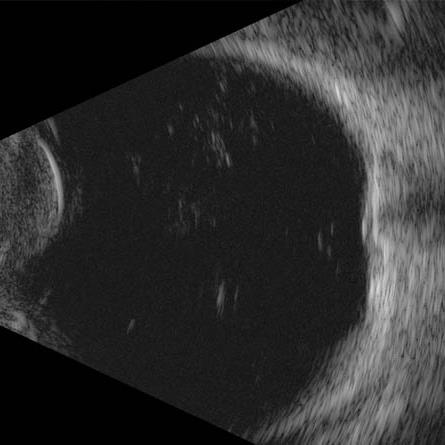

Ultrassonografia Ocular